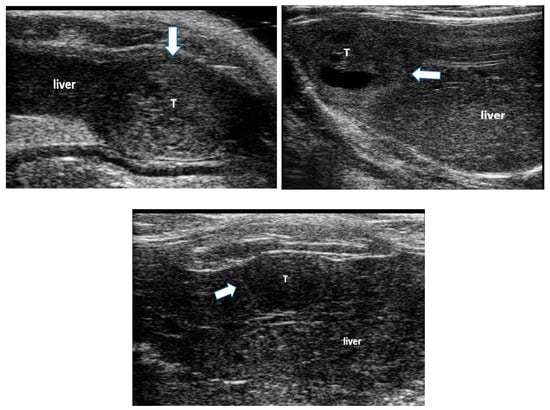

All animals developed liver disease and multiple foci of hepatocellular carcinoma (HCC), seen on B-mode ultrasound imaging (Figure 1). These tumors were associated with liver changes including increased echogenicity and coarseness of the image texture, indicating liver fibrosis and cirrhosis [,], ascites and hepatosplenomegaly.

Figure 1. Examples of hepatocellular carcinoma (HCC) tumors developed in the liver of rats following ingestion of diethylnitroseamine (DEN) for 12 weeks. The white arrows point to HCC tumors (T) surrounded by liver tissue. Liver tissue is hyper-echoic and coarse due to the cirrhotic changes.